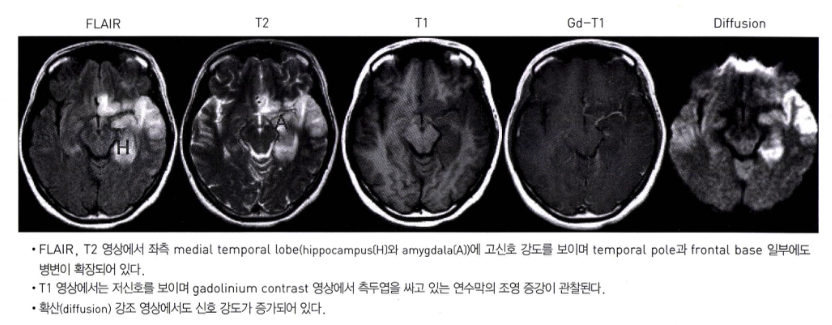

• 단순포진 뇌염 (HSV encephalitis): 가장 심각한 합병증. 측두엽(temporal lobe)을 주로 침범하며, 발열, 의식 변화, 경련 등을 보임